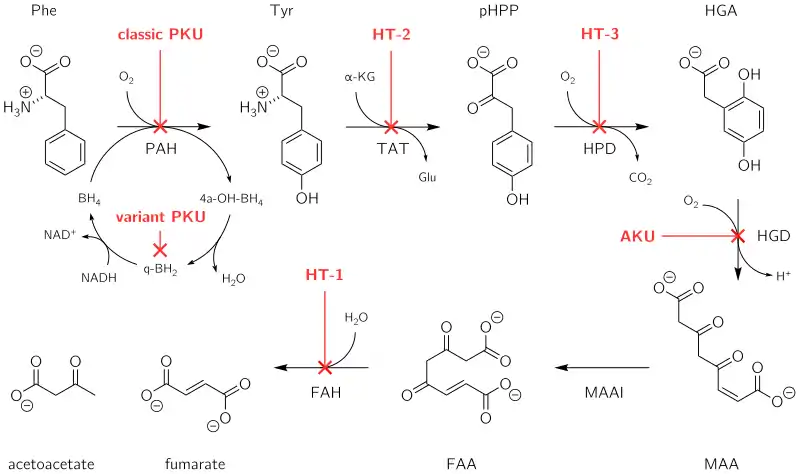

Alkaptonuria is a rare inherited genetic disease which is caused by a mutation in the HGD gene for the enzyme homogentisate 1,2-dioxygenase (EC 1.13.11.5); if a person inherits an abnormal copy from both parents (it is a recessive condition), the body accumulates an intermediate substance called homogentisic acid in the blood and tissues. Homogentisic acid and its oxidized form alkapton are excreted in the urine, giving it an unusually dark color. The accumulating homogentisic acid causes damage to cartilage (ochronosis, leading to osteoarthritis) and heart valves, as well as precipitating as kidney stones and stones in other organs. Symptoms usually develop in people over 30 years old, although the dark discoloration of the urine is present from birth.

All people carry in their DNA two copies (one received from each parent) of the gene HGD, which contains the genetic information to produce the enzyme homogentisate 1,2-dioxygenase (HGD) which can normally be found in numerous tissues in the body (liver, kidney, small intestine, colon, and prostate). In people with alkaptonuria, both copies of the gene contain abnormalities that mean that the body cannot produce an adequately functioning enzyme.[4] HGD mutations are generally found in certain parts (exons 6, 8, 10, and 13), but a total of over 100 abnormalities has been described throughout the gene.[4] The normal HGD enzyme is a hexamer (it has six subunits) that are organized in two groups of three (two trimers) and contains an iron atom. Different mutations may affect the structure, function, or solubility of the enzyme.[4] Very occasionally, the disease appears to be transmitted in an autosomal-dominant fashion, where a single abnormal copy of HGD from a single parent is associated with alkaptonuria; other mechanisms or defects in other genes possibly are responsible in those cases.[4]

The HGD enzyme is involved in the metabolism (chemical processing) of the aromatic amino acids phenylalanine and tyrosine. Normally, these enter the bloodstream through protein-containing food and the natural turnover of protein in the body. Tyrosine is specifically required for a number of functions, such as hormones (e.g. thyroxine, the thyroid hormone), melanin (the dark pigment in the skin and hair), and certain proteins, but the vast majority (over 95%) is unused and is metabolized through a group of enzymes that eventually generate acetoacetate and malate.[1] In alkaptonuria, the HGD enzyme cannot metabolize the homogentisic acid (generated from tyrosine) into 4-maleylacetoacetate, and homogentisic acid levels in the blood are 100-fold higher than would normally be expected, despite the fact that a substantial amount is eliminated into the urine by the kidneys.[1]